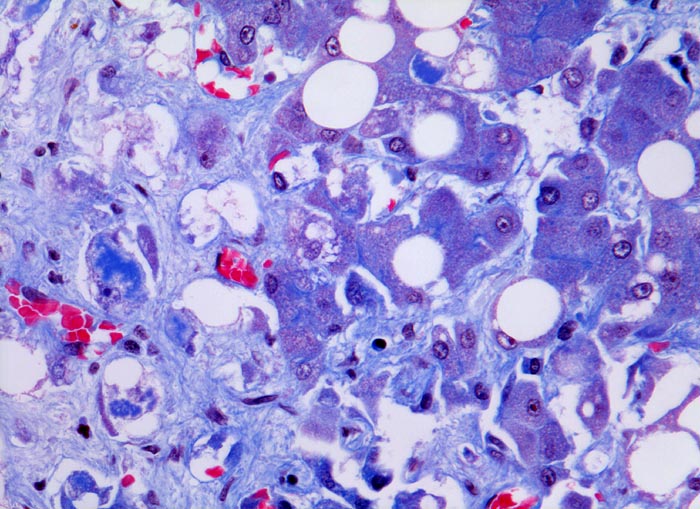

aethylische Leberzirrhose: Mallory-Denk Körper und Steatose

An der Parenchym/Bindegewebsgrenze Hepatozyten mit intrazytoplasmatischen Mallory-Denk Körpern: Irregulär begrenzte, pfützenartige, hirschgeweihartige oder raupenförmige blaue Zytoplasmastrukturen. Andere Hepatozyten enthalten eine grosse Fettvakuole, welche den Kern zur Seite verdrängt (grobtropfige Verfettung). Vereinzelt ist eine feintropfige Verfettung nachweisbar mit multiplen intrazytoplasmatischen Fetttropfen.

Mallory Körper entsprechen intrazytoplasmatischen Ablagerungen von kollabiertem Zytoskelett (Intermediärfilamenten), das zusammen mit ubiquitinierten Proteinen wie Heat Shock Proteinen kondensiert. Sie finden sich in nicht verfetteten Hepatozyten und sind typischerweise hirschgeweihförmig. Immunhistochemisch färben sich die Mallory Körper mit Ubiquitin an. Vorkommen von Mallory Körpern bei alkoholischem Leberschaden, Autoimmunhepatitis, Cholestase, Medikamentös toxischem Leberschaden, hepatozellulärem Karzinom, nicht alkoholischer Steatohepatitis, PBC, PSC und Morbus Wilson.